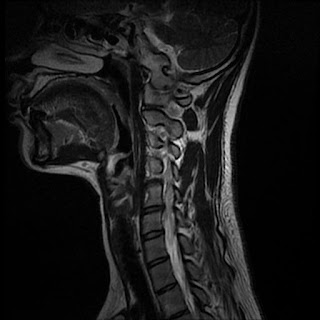

And functionalther was no abnormality seen. To code a diagnosis of this type, you must use specify a 7th character that describes the diagnosis 'wedge compression fracture of unspecified thoracic vertebra' in more detail. The fracture line breaches both the anterior and posterior vertebral body cortex and the anterior superior endplate.

805.0 compression fracture (c1 or c2) 805.1 compression fracture (cervical) 805.2 compression fracture.

Thoracic compression fracture versus lumbar compression fracture. What is the difference between an icd9 code and a cpt code? Information about and icd cm diagnosis code ,x. Example, percent compression or retropulsion of bone is. Compression fractures of the back. And functionalther was no abnormality seen. 1511 malignant neo pylorus 1512 mal neo pyloric antrum 1513 mal neo stomach fundus 1514 mal neo stomach body 1515 mal neo stom lesser curv 1516 mal neo stom great curv. Related online courses on physioplus. Be the first to answer! Compression fracture is when the bones in the spine (vertebrae) collapse. At two months from injury, the fracture is probably still not fully stable as compression fractures take about 3 months to heal. Centers for medicare and medicaid services. 733.19 pathologic fracture of other specified site. Thoracic compression fracture versus lumbar compression fracture. Lateral femoral cutaneous neuropathy (meralgia paresthetica). Be careful not to load your spine. The 7th characters that can be added, and the resulting billable codes, are as follows